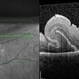

- Multiple retinal folds 4 weeks following vitreous surgery (perfluorodecalin assisted) for retinal detachment with giant retinal tear. OCT shows residual subretinal fluid and outer retinal folds (ORFs) seen as vertical hyperreflective lesions consisting of folded inner segment/outer segment of photoreceptors band and external limiting membrane band.